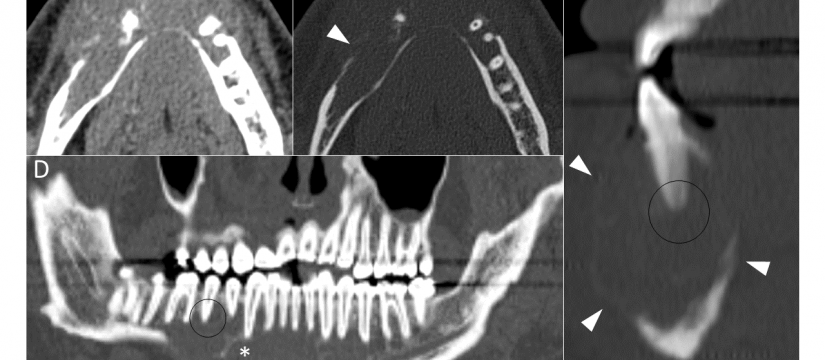

Mujer de 69 años de edad, con un cuadro de 7 meses de inestabilidad cefálica y de la marcha. Se realiza una RM craneal inicial, que es normal. Progresivamente, la síntomatología empeora, añadiéndose desorientación, alucinaciones, mioclonías y deterioro cognitivo. Se repite RM craneal por empeoramiento clínico progresivo.